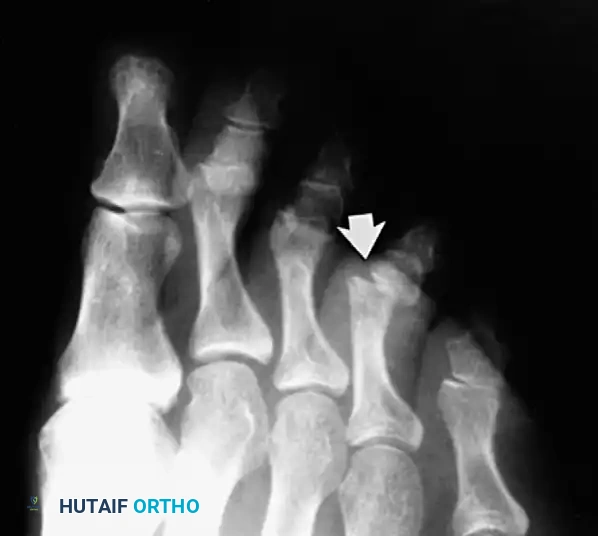

Post-Reduction Evaluation:

Post-reduction radiographs are mandatory. If the radiograph demonstrates residual widening of the joint space, the surgeon must assume the plantar plate remains incarcerated. This is an absolute indication for open reduction, even if the toe appears clinically straight.

Fig. 86-52 Interphalangeal joint space remains wider than normal after closed reduction; this is an indication for open reduction. (From Miki T, Yamamuro T, Kitai T: An irreducible dislocation of the great toe: report of two cases and review of the literature, Clin Orthop Relat Res 230:200, 1988.)